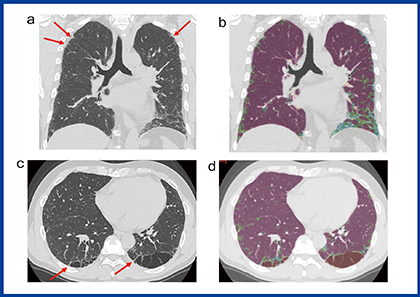

QZIP-ILDは,人工知能(AI)を用いて間質性肺炎の胸部CTの領域分割を行うソフトウエアである。約100症例の間質性肺炎のCT画像から1000個以上のサンプルを抽出し,ニューラルネットワークで解析した。100症例のラベリングは,正常,肺気腫,すりガラス影,網状影,牽引性気管支拡張,線維化,コンソリデーション,蜂巣肺について3方向(軸位断,冠状断,矢状断)で行った。特発性肺線維症(idiopathic pulmonary fibrosis:IPF)の症例でのQZIP-ILDの解析結果を図2に示す。典型的な症例では,IPFのCT画像は通常型間質性肺炎(usual interstitial pneumonia:UIP)パターンを示すが,UIPの初期像は胸膜直下のとげ状のごく小さい病変であることが知られ見逃しやすい(図2 a,b)。QZIP-ILDでは,特にこの胸膜直下の病変を抽出できるようにラベリングした。また,喫煙者では肺気腫と間質性肺炎が併存することもよくあるが,肺気腫の壁が線維化で厚く見えることもしばしば経験する。こうした囊胞壁の線維化もできるだけ抽出できるようにラベリングした(図2c,d)。

図2 特発性肺線維症のCT画像とQZIP-ILDの解析結果

症例上(a, b) 60歳代,男性,上葉の胸膜直下の線維化と思われる小さなとげ状の構造(a→)もQZIP-ILDで検出できている。

症例下(c, d) 60歳代,男性,囊胞状の気腫状肺の辺縁部分の線維化と思われる索状構造(c→)もQZIP-ILDで検出できている。

* QZIP-ILDの色の説明:ピンク=正常,茶色=気腫状肺,黄緑=すりガラス影,水色=網状影,緑=牽引性気管支拡張,黄色=無気肺硬化型の線維化,オレンジ=コンソリデーション,紫=蜂巣肺